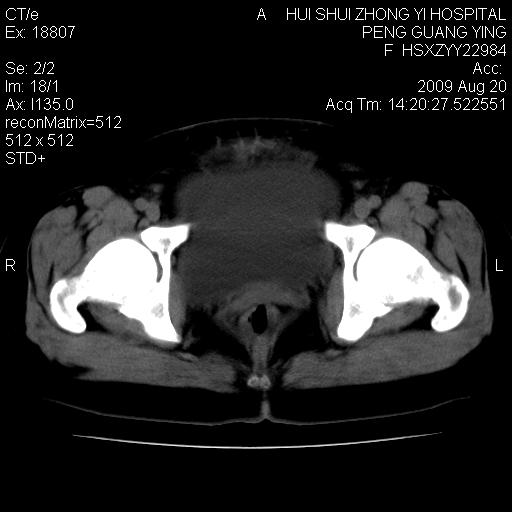

标题: CT21707:女,42岁,因发现下腹部包块2月。 [打印本页]

标题: CT21707:女,42岁,因发现下腹部包块2月。

目前的影像表现显示肿块位于腹腔及盆腔,但具体定位,分清来源较困难,是否来源于卵巢、子宫无法定论,子宫直肠及子宫膀胱周围脂肪间隙尚较清晰,如果患者有过腹腔好或者盆腔手术史,也可以形成不典型的血中,最好手术后定为定性,我期待结果。

来源卵巢--畸胎类肿瘤

病史不全面,病灶来源可能是子宫或卵巢,若临床有剖腹产、痛经史,则更支持前者,亦更支持子宫腺肌症